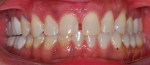

When passion becomes your profession..making people smile becomes your habit! here’s my recent case of cosmetic dentistry: